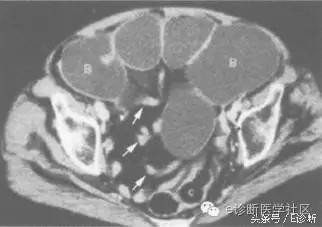

表现:为扭转性肠梗阻CT征象,扩张的肠襻在梗阻部位逐渐变尖,肠襻收缩至一点,形似鸟嘴。解释:肠梗阻时萎陷肠管与扩张肠管之间形成移行部,扩张肠管向萎陷部肠管的突出部分,形似鸟嘴,即为鸟嘴征。

当扫描层面通过闭襻时可表现为2个扩张的肠环,随层面逐渐靠近闭襻根部,可见2个相邻肠环的距离逐渐接近;当扫描层面通过闭襻的根部时,可见肠管的变形,肠扭转时则表现为三角形的软组织密度影;当闭襻与扫描层面平行时,则表现为1个扩张的U形肠襻;扫描层面通过闭襻的输入与输出端时,则表现为相邻的2个萎陷肠环。当肠扭转闭襻的输入或输出段肠管的长轴与CT扫描层面平行时,由于扭转使输入段逐渐变细,输出段由细变粗,在CT图像上表现为鸟嘴征。肠扭转时的光滑鸟嘴征,可因梗阻处肠壁的水肿增厚和肠系膜的充血、水肿,变为锯齿状的鸟嘴征。

可见小肠襻扩张,其内充满液体,在梗阻部位逐渐边尖,肠襻收缩至一点,形似鸟嘴(最上方白箭)